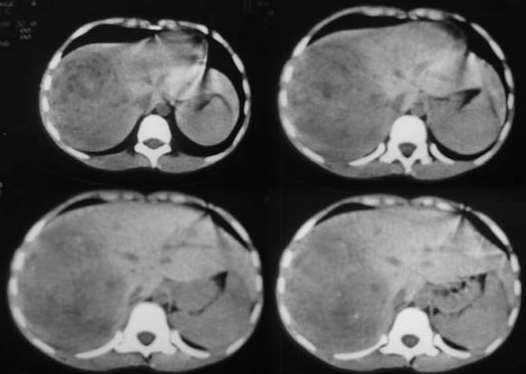

患者男性,10岁,腹痛4小时余,5年前患乙肝.查:右上腹压痛(+),反跳痛(+)血常规:wbs13.5x10(9)/l,b超提示:右肝实质性占位,性质待查.afp弱阳性患者男性,10岁,腹痛4小时余,5年前患乙肝.查:右上腹压痛(+),反跳痛(+)血常规:wbs13.5x10(9)/l,b超提示:右肝实质性占位,性质待查.afp弱阳性.

由于拍照技术不熟悉,图象模糊,请大家原谅!!

肝右叶巨大类圆形混杂密度影,边缘清晰,病变内部密度不均匀,可见环形钙化,我们考虑肝脏恶性肿瘤,肝母细胞瘤或肝细胞癌.请大家就平扫给予分析和指教.谢谢!!患者直接上省级医院检查,未做增强!

肝影增大,肝右叶巨大类圆形混杂密度影,边缘清晰,病变内部密度不均匀,可见环形钙化,我们考虑肝脏恶性肿瘤,肝母细胞瘤可能性大,有乙肝病史肝细胞癌不完全除外。!

肝右叶巨大类圆形混杂密度影,边缘清晰,病变内部密度不均匀,可见环形钙化,结合临床考虑肝母细胞瘤可能性大。